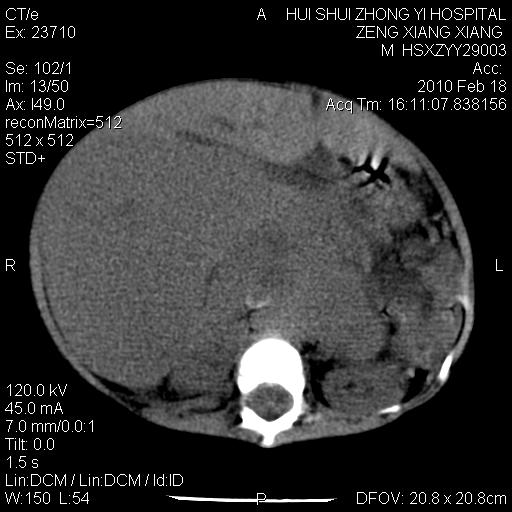

标题: PED3106:男,2岁,腹胀1月。 [打印本页]

标题: PED3106:男,2岁,腹胀1月。

定位腹膜后,肾上腺来源;

定性:恶性神经源性,肾上腺神经节母细胞瘤可能性大。

鉴别:肝母、肾母、肝脏中胚层错构瘤。

依据:年龄、有钙化,肾脏及肝脏受压移位。

肝母细胞瘤可能性大,右肾形态大体可见,不支持肾母细胞瘤,右肾移位不明显,肾上腺神经母细胞瘤可能性不大。